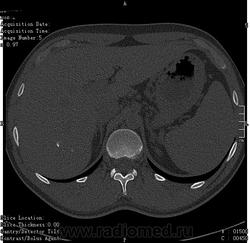

- https://radiomed.ru/sites/default/files/styles/case_slider_image/public/user/16314/ct.1.002.jpg?itok=n00uCisV

- https://radiomed.ru/sites/default/files/styles/case_slider_image/public/user/16314/ct.1.005.jpg?itok=tL-o0Zyd

- https://radiomed.ru/sites/default/files/styles/case_slider_image/public/user/16314/ct.1.006.jpg?itok=eD2B8PpJ

- https://radiomed.ru/sites/default/files/styles/case_slider_image/public/user/16314/ct.1.009_0.jpg?itok=t616c8pc

- https://radiomed.ru/sites/default/files/styles/case_slider_image/public/user/16314/ct.1.013.jpg?itok=naYfaJaK

- https://radiomed.ru/sites/default/files/styles/case_slider_image/public/user/16314/ct.1.016.jpg?itok=7QI04EsU

- https://radiomed.ru/sites/default/files/styles/case_slider_image/public/user/16314/ct.1.017.jpg?itok=EJmrsm0z

- https://radiomed.ru/sites/default/files/styles/case_slider_image/public/user/16314/ct.1.019.jpg?itok=KMCM7VHI

- https://radiomed.ru/sites/default/files/styles/case_slider_image/public/user/16314/ct.1.020.jpg?itok=m1jAA0ZW

- https://radiomed.ru/sites/default/files/styles/case_slider_image/public/user/16314/ct.1.021.jpg?itok=i89Jb3je

- https://radiomed.ru/sites/default/files/styles/case_slider_image/public/user/16314/ct.1.025.jpg?itok=UWwwyZZY

- https://radiomed.ru/sites/default/files/styles/case_slider_image/public/user/16314/ct.1.026.jpg?itok=FQfAszqG

- https://radiomed.ru/sites/default/files/styles/case_slider_image/public/user/16314/ct.1.027.jpg?itok=qJa3vYdf

- https://radiomed.ru/sites/default/files/styles/case_slider_image/public/user/16314/ct.1.028.jpg?itok=LjsabUNE

- https://radiomed.ru/sites/default/files/styles/case_slider_image/public/user/16314/ct.1.031.jpg?itok=cV37-2V6

- https://radiomed.ru/sites/default/files/styles/case_slider_image/public/user/16314/ct.1.032.jpg?itok=MrYi5Lda

- https://radiomed.ru/sites/default/files/styles/case_slider_image/public/user/16314/ct.1.033.jpg?itok=t7V0JYJY

- https://radiomed.ru/sites/default/files/styles/case_slider_image/public/user/16314/ct.1.038.jpg?itok=qu-97Yhs

- https://radiomed.ru/sites/default/files/styles/case_slider_image/public/user/16314/ct.1.039.jpg?itok=-aeLLBFV

Не понятно, вроде инородные тельца. Либо кальцинаты. Образования в печени не вижу. А какое тут может быть заключение, кроме кальцинатов? Признаков сосудистой опухоли (флеболиты) или любой иной опухоли , паразитарной кисты не вижу.

Кальцинаты в печени редкое явление. Вопрос мало изучен. Теоретически это последствие перенесенной инекции. Есть вариант, что могут метазстазы обызвествляться. Но в практике таких тотально кальцинированых метастазов не видел. Так что, если ничего не беспокоит, взять на контроль и забыть.

Ну, природа кальцинатов в печени может быть очень различна.

но вообще если они не сочетаются или не являются компонентами допонительных образований, характер которых требует уточнения, не увеличиваются при динамическом наблюдении и не находятся внутри желчных протоков - про них можно забыть.

"Although a wide variety of causes of hepatic calcification has been described (Table 1), the most common causes are calcified granulomas and hydatid cysts, followed by calcification as- sociated with hepatic neoplasms (3). Other ori- gins of calcification include vascular and biliary causes. "